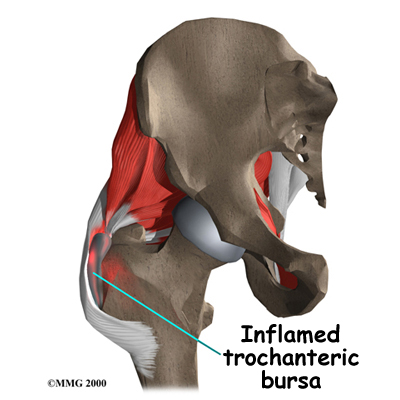

Здоровье суставов: Трохантерит и его влияние на мышцы